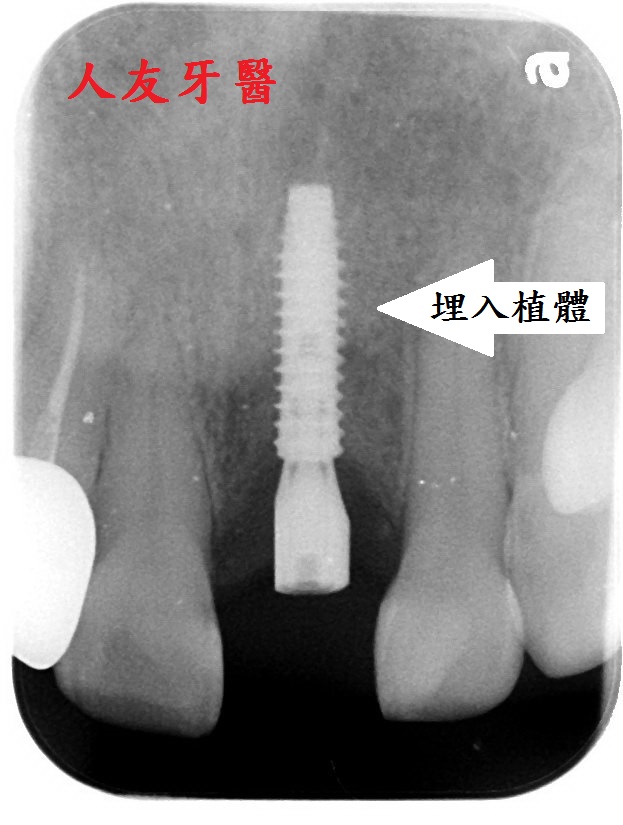

拔牙後,等待植牙區的骨頭與牙肉都長的豐滿後再進行植牙手術

埋入植體後,待植牙骨密度到達標準值後再利用電腦掃描製作全鋯牙冠膺復

(三)植入人工牙根(植體):待齒槽骨狀況良好即

可埋入植體,需3~6個月時間進行骨整合,

讓植體與齒槽骨緊密結合